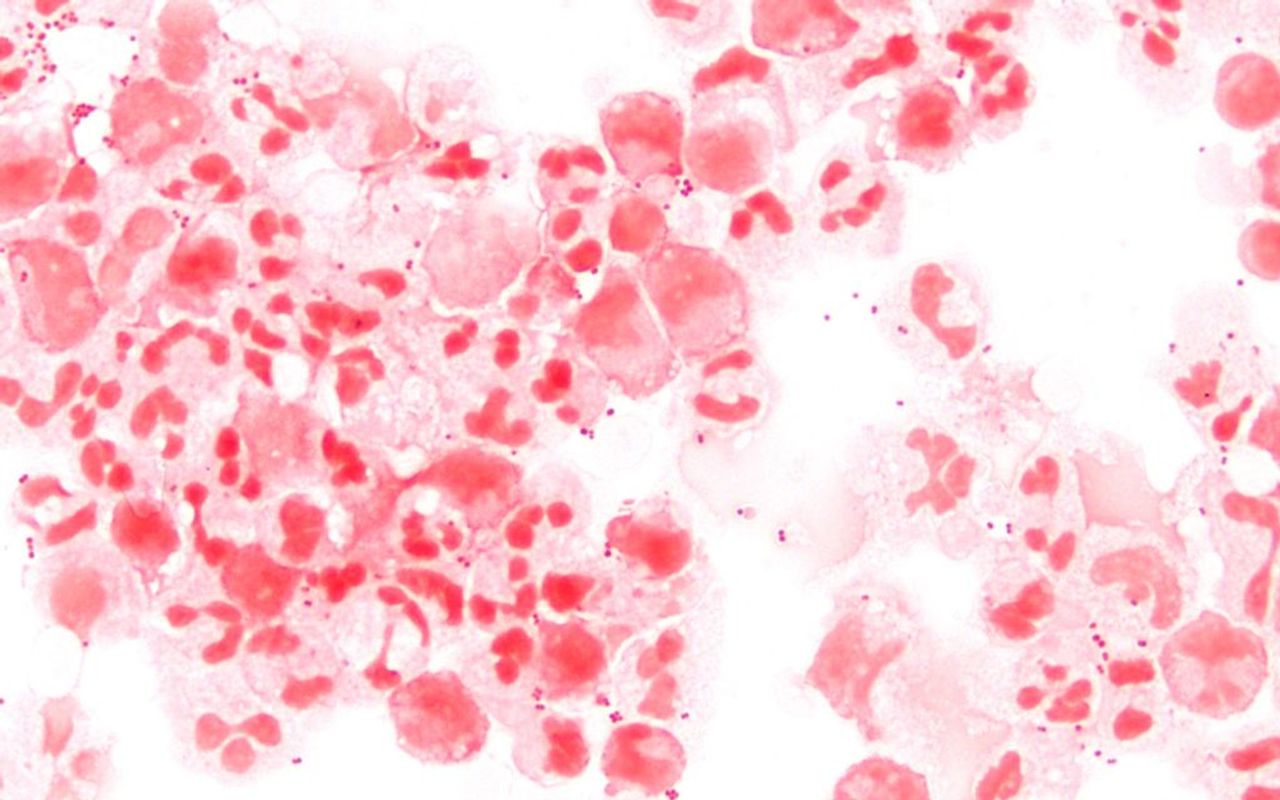

MenB is now the most common form of the illness, which accounted for four out of every five meningitis cases in the UK last year. The culprit is a bacterium known as meningococcus or Neisseria meningitidis, which lives in 10 percent of people’s throats at any one time. It is only a problem if it invades the blood or spinal fluid, leading to infection of the protective lining of the spinal cord.